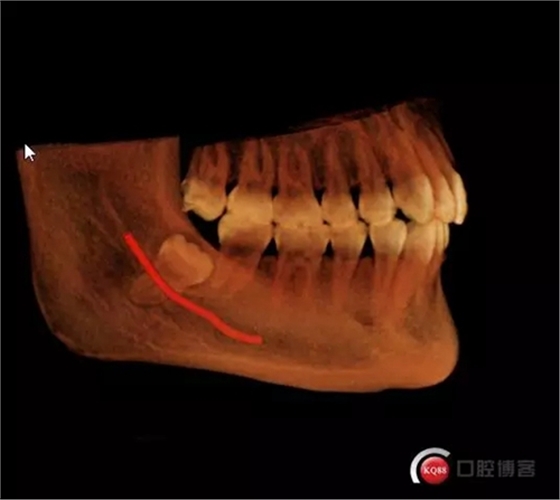

1498615671_453909.png

術(shù)前曲面斷層